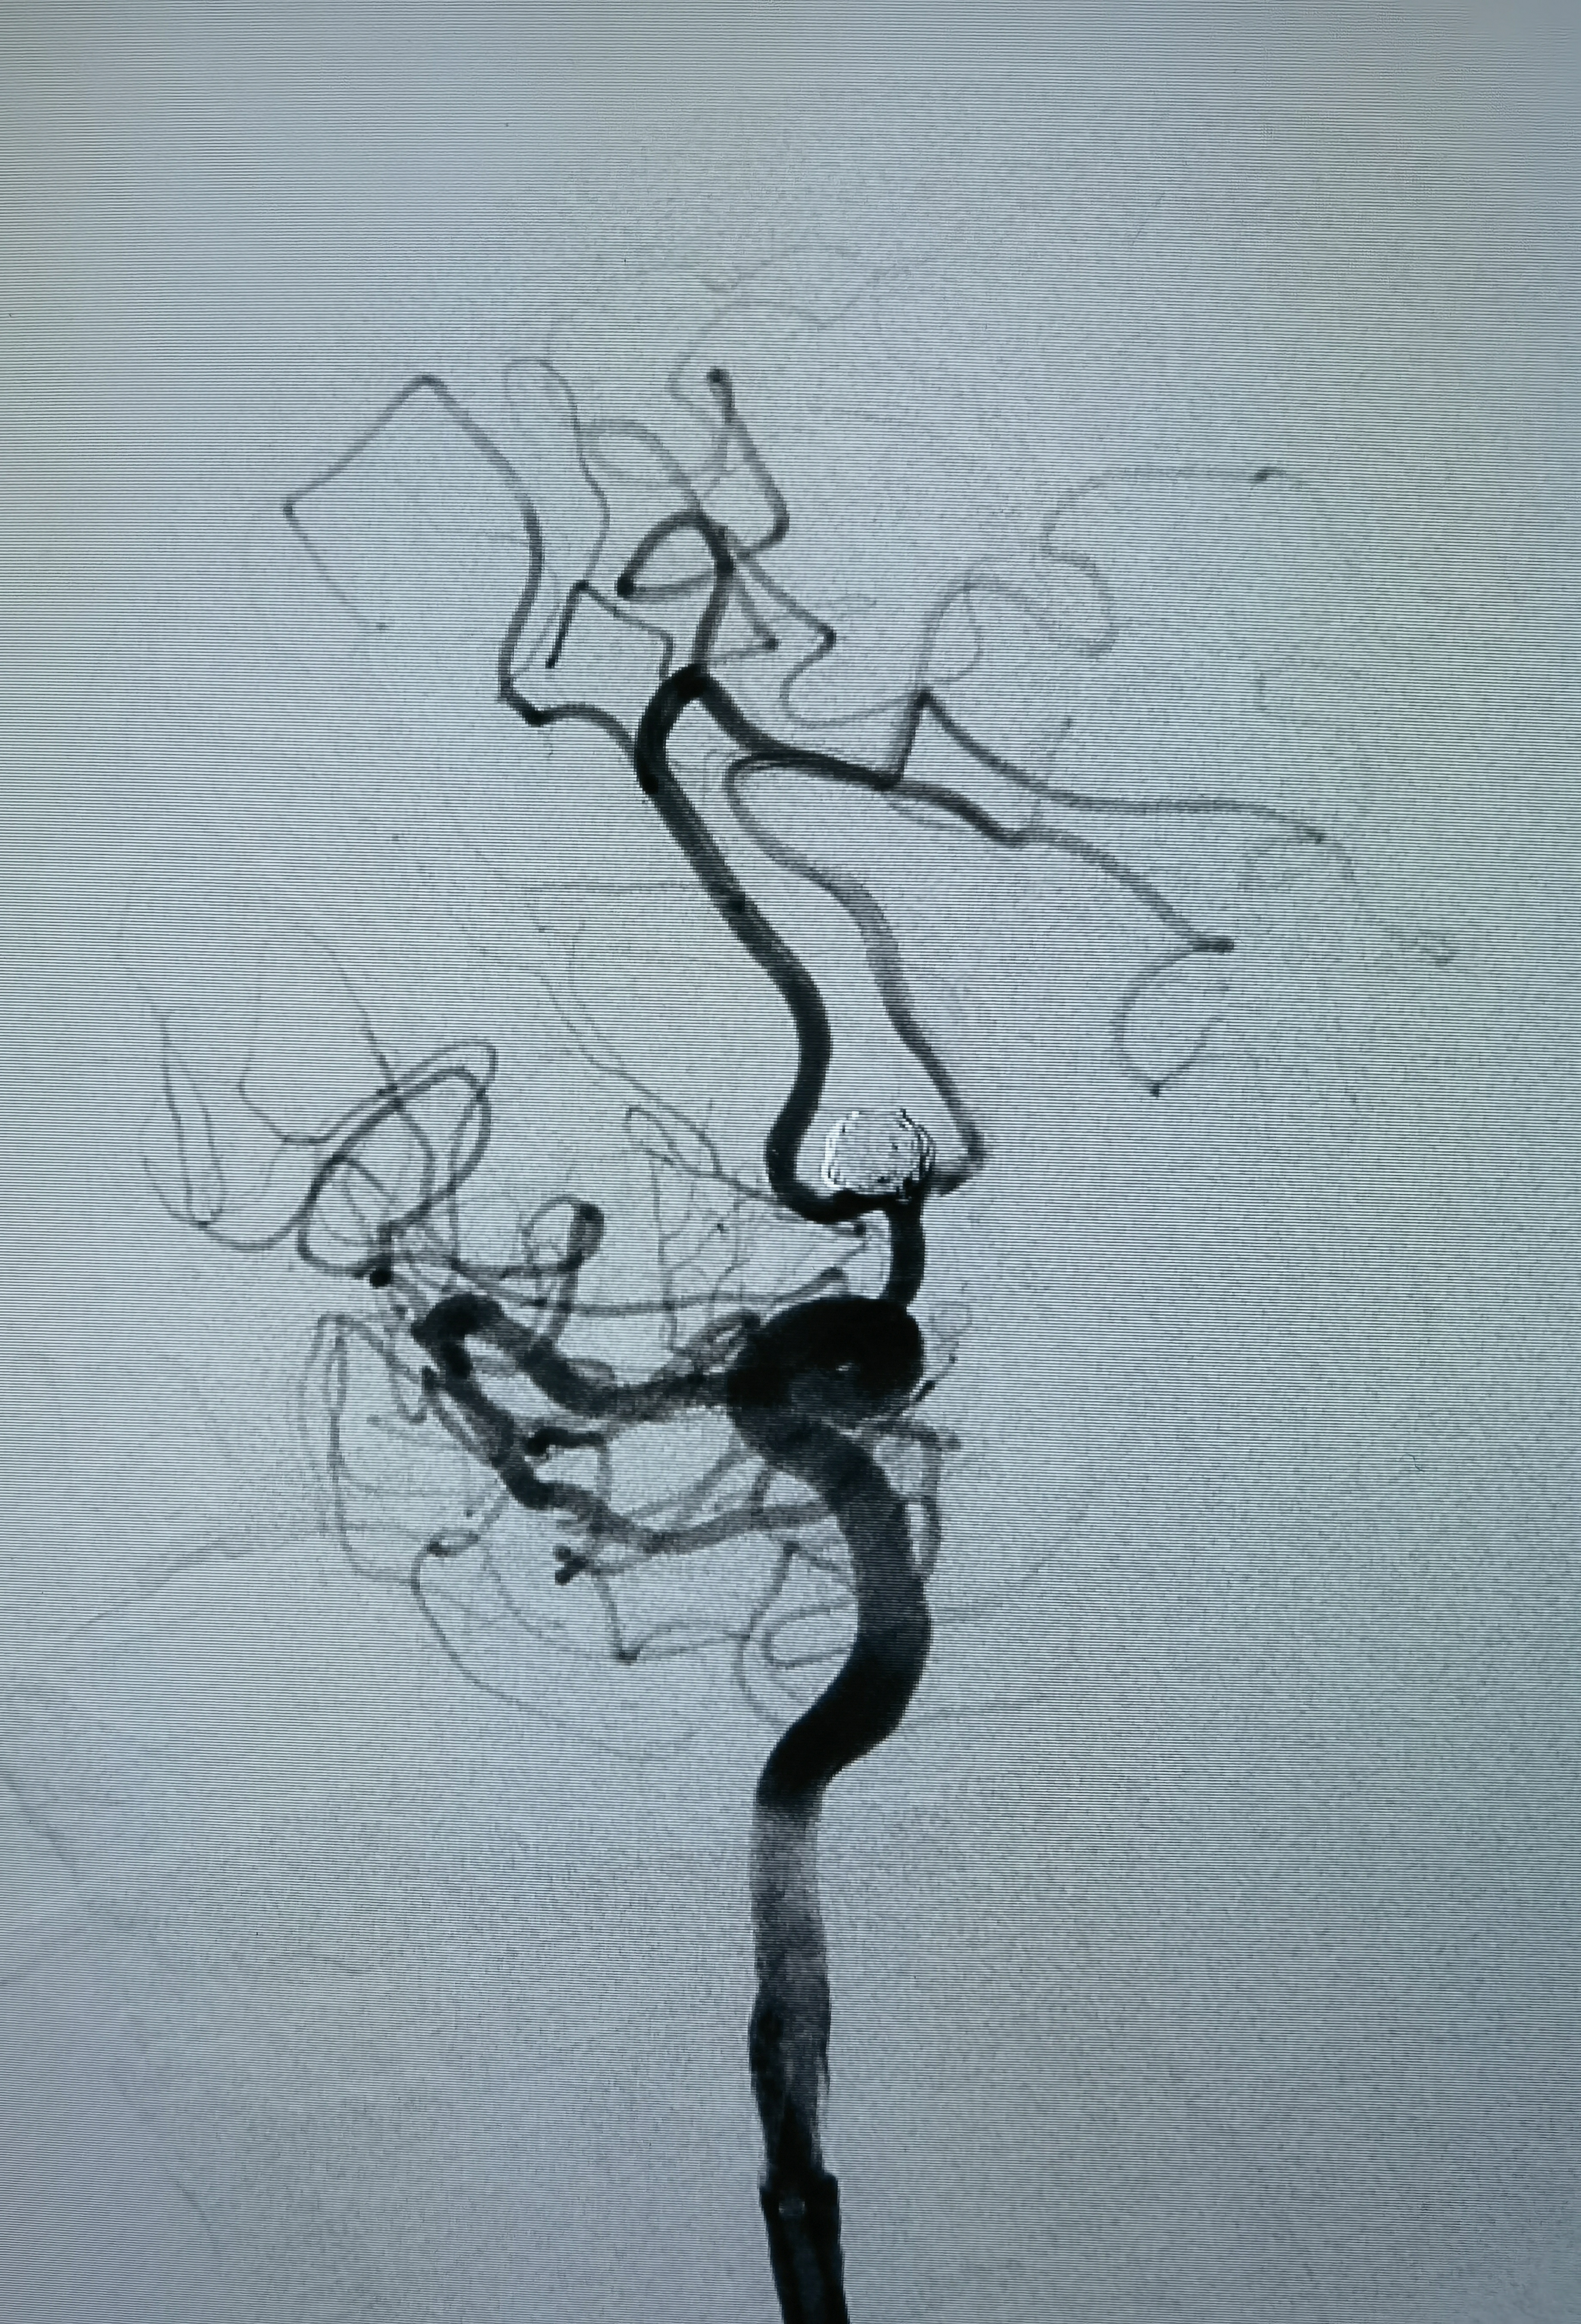

女性,63岁,体检发现动脉瘤,造影显示动脉瘤带子囊,破裂风险大,手术干预!

正位造影